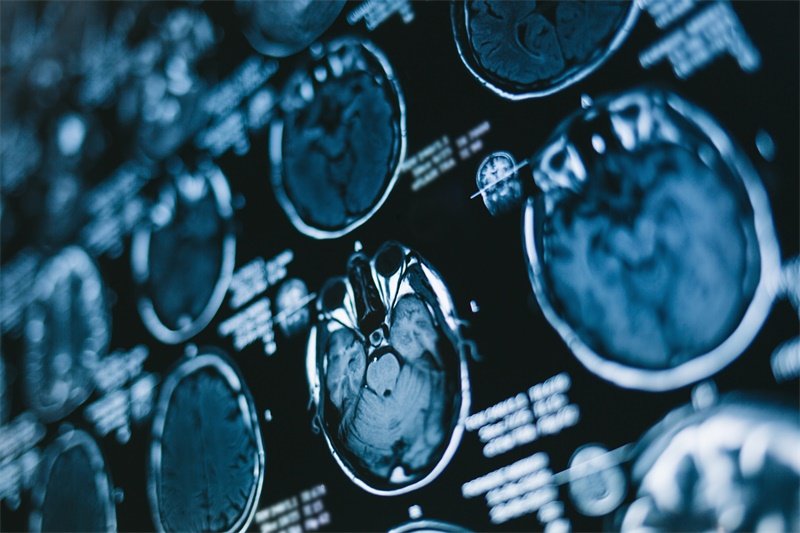

影像学特征

影像学在大脑镰旁多发占位胶质瘤的诊断中起着至关重要的作用。磁共振成像(MRI)是首选的影像学检查方式,能够清晰显示肿瘤的部位、大小及周围结构的受压情况。

在MRI上,胶质瘤通常表现为高信号和边界不清的病灶,伴随有明显的水肿。增强扫描显示出肿瘤的血供特点,可以帮助判断肿瘤的侵袭性及与周围组织的关系。